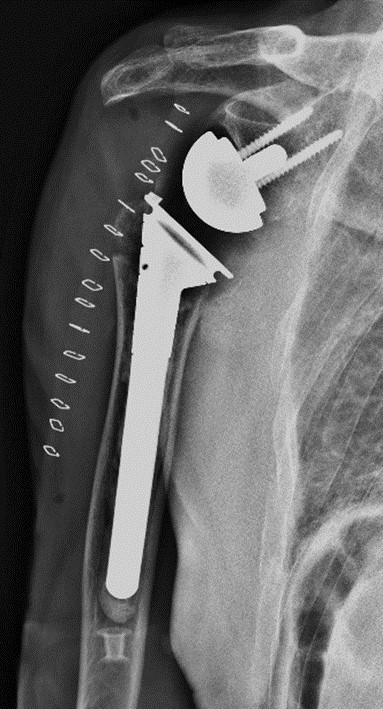

在麻醉手术科、输血科等科室的全力配合下,王亮副主任医师团队顺利取出骨折块,精确处理大小结节,安装关节假体,重建了肩关节的稳定性,整个手术过程顺利。术后复查X线提示假体位置良好,关节对位满意。

术后复查X线片示关节假体位置良好